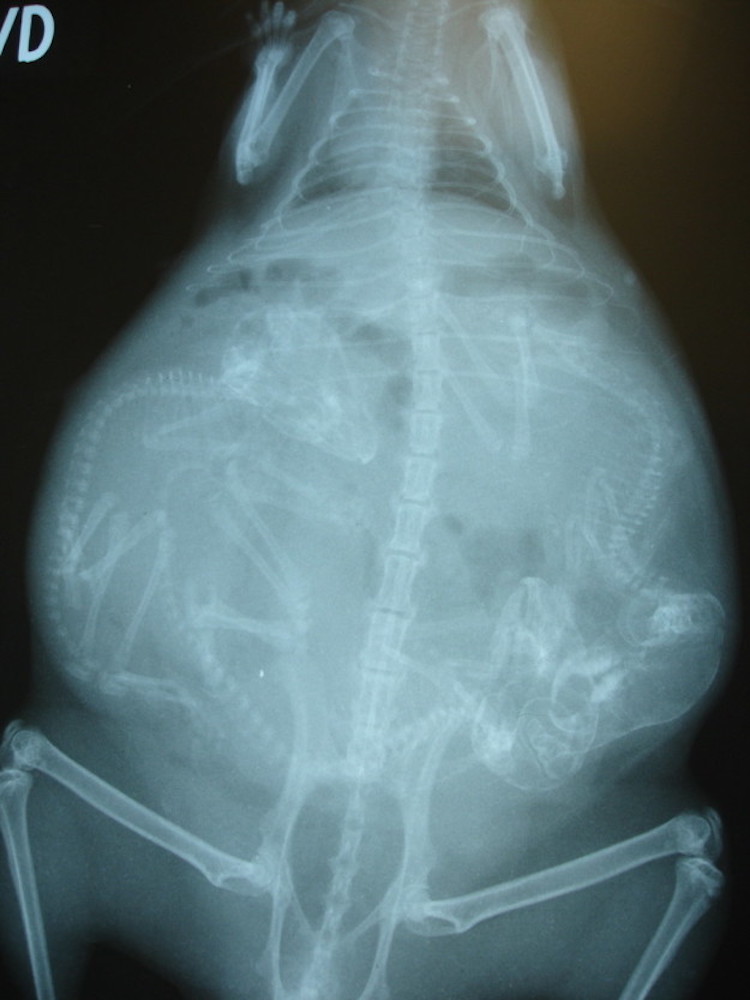

3 – Chatte enceinte. Les chattes peuvent tomber enceinte à 4 mois. À environ 45 jours de grossesse, les squelettes des chatons sont assez formés pour être visibles aux rayons X.